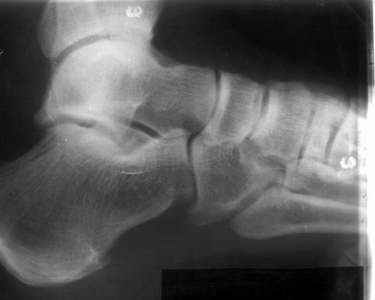

братился мужчина, 50 лет. Жалобы на боли в голеностопном суставе, периодическое подворачивание стопы вовнутрь. Получил травму 5 лет назад. При осмотре - признаки латеральной нестабильности, боли по ходу малоберцово-таранной, задней малоберцово-пяточной связки. Сделал стандартный Rg, и Rg с нагрузкой. В течение последнего года начали беспокоить боли в коленном, тазобедренном суставе. Как полагаю, это связано с нарушением биомеханики всей ноги. Если прооперировать и устранть нестабильность, пройдут ли эти боли (этот вопрос пациент задал сразу, как только услышал слово операция)? С ув. Сергей Мелашенко, Приморск, Запорожская обл. Ukraine

Попробуйте сделать аналогичный стресс -снимок прямой проекции здорового сустава и сравнив его с ранее травмированной стороной определитесь есть

нестабильность или нет.

присоединяюсь к мнению показать симметричные снимки

пока не кажется, что нестабильность очевидна.